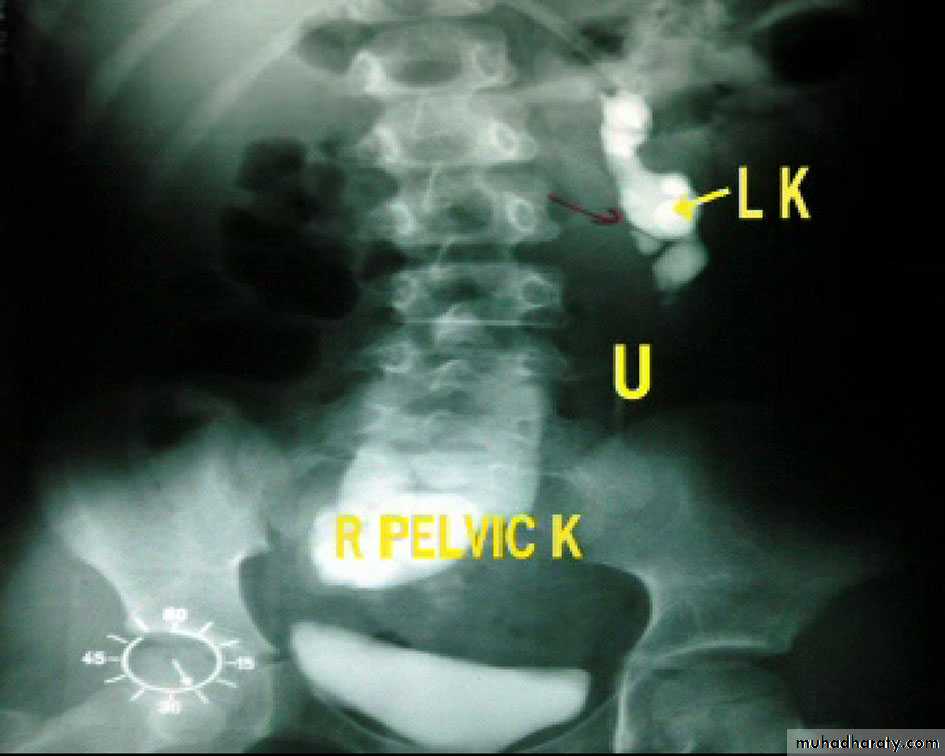

15- Ectopic

17- Ectopic + hydronephrosis

19- Ectopic + hydronephrosis